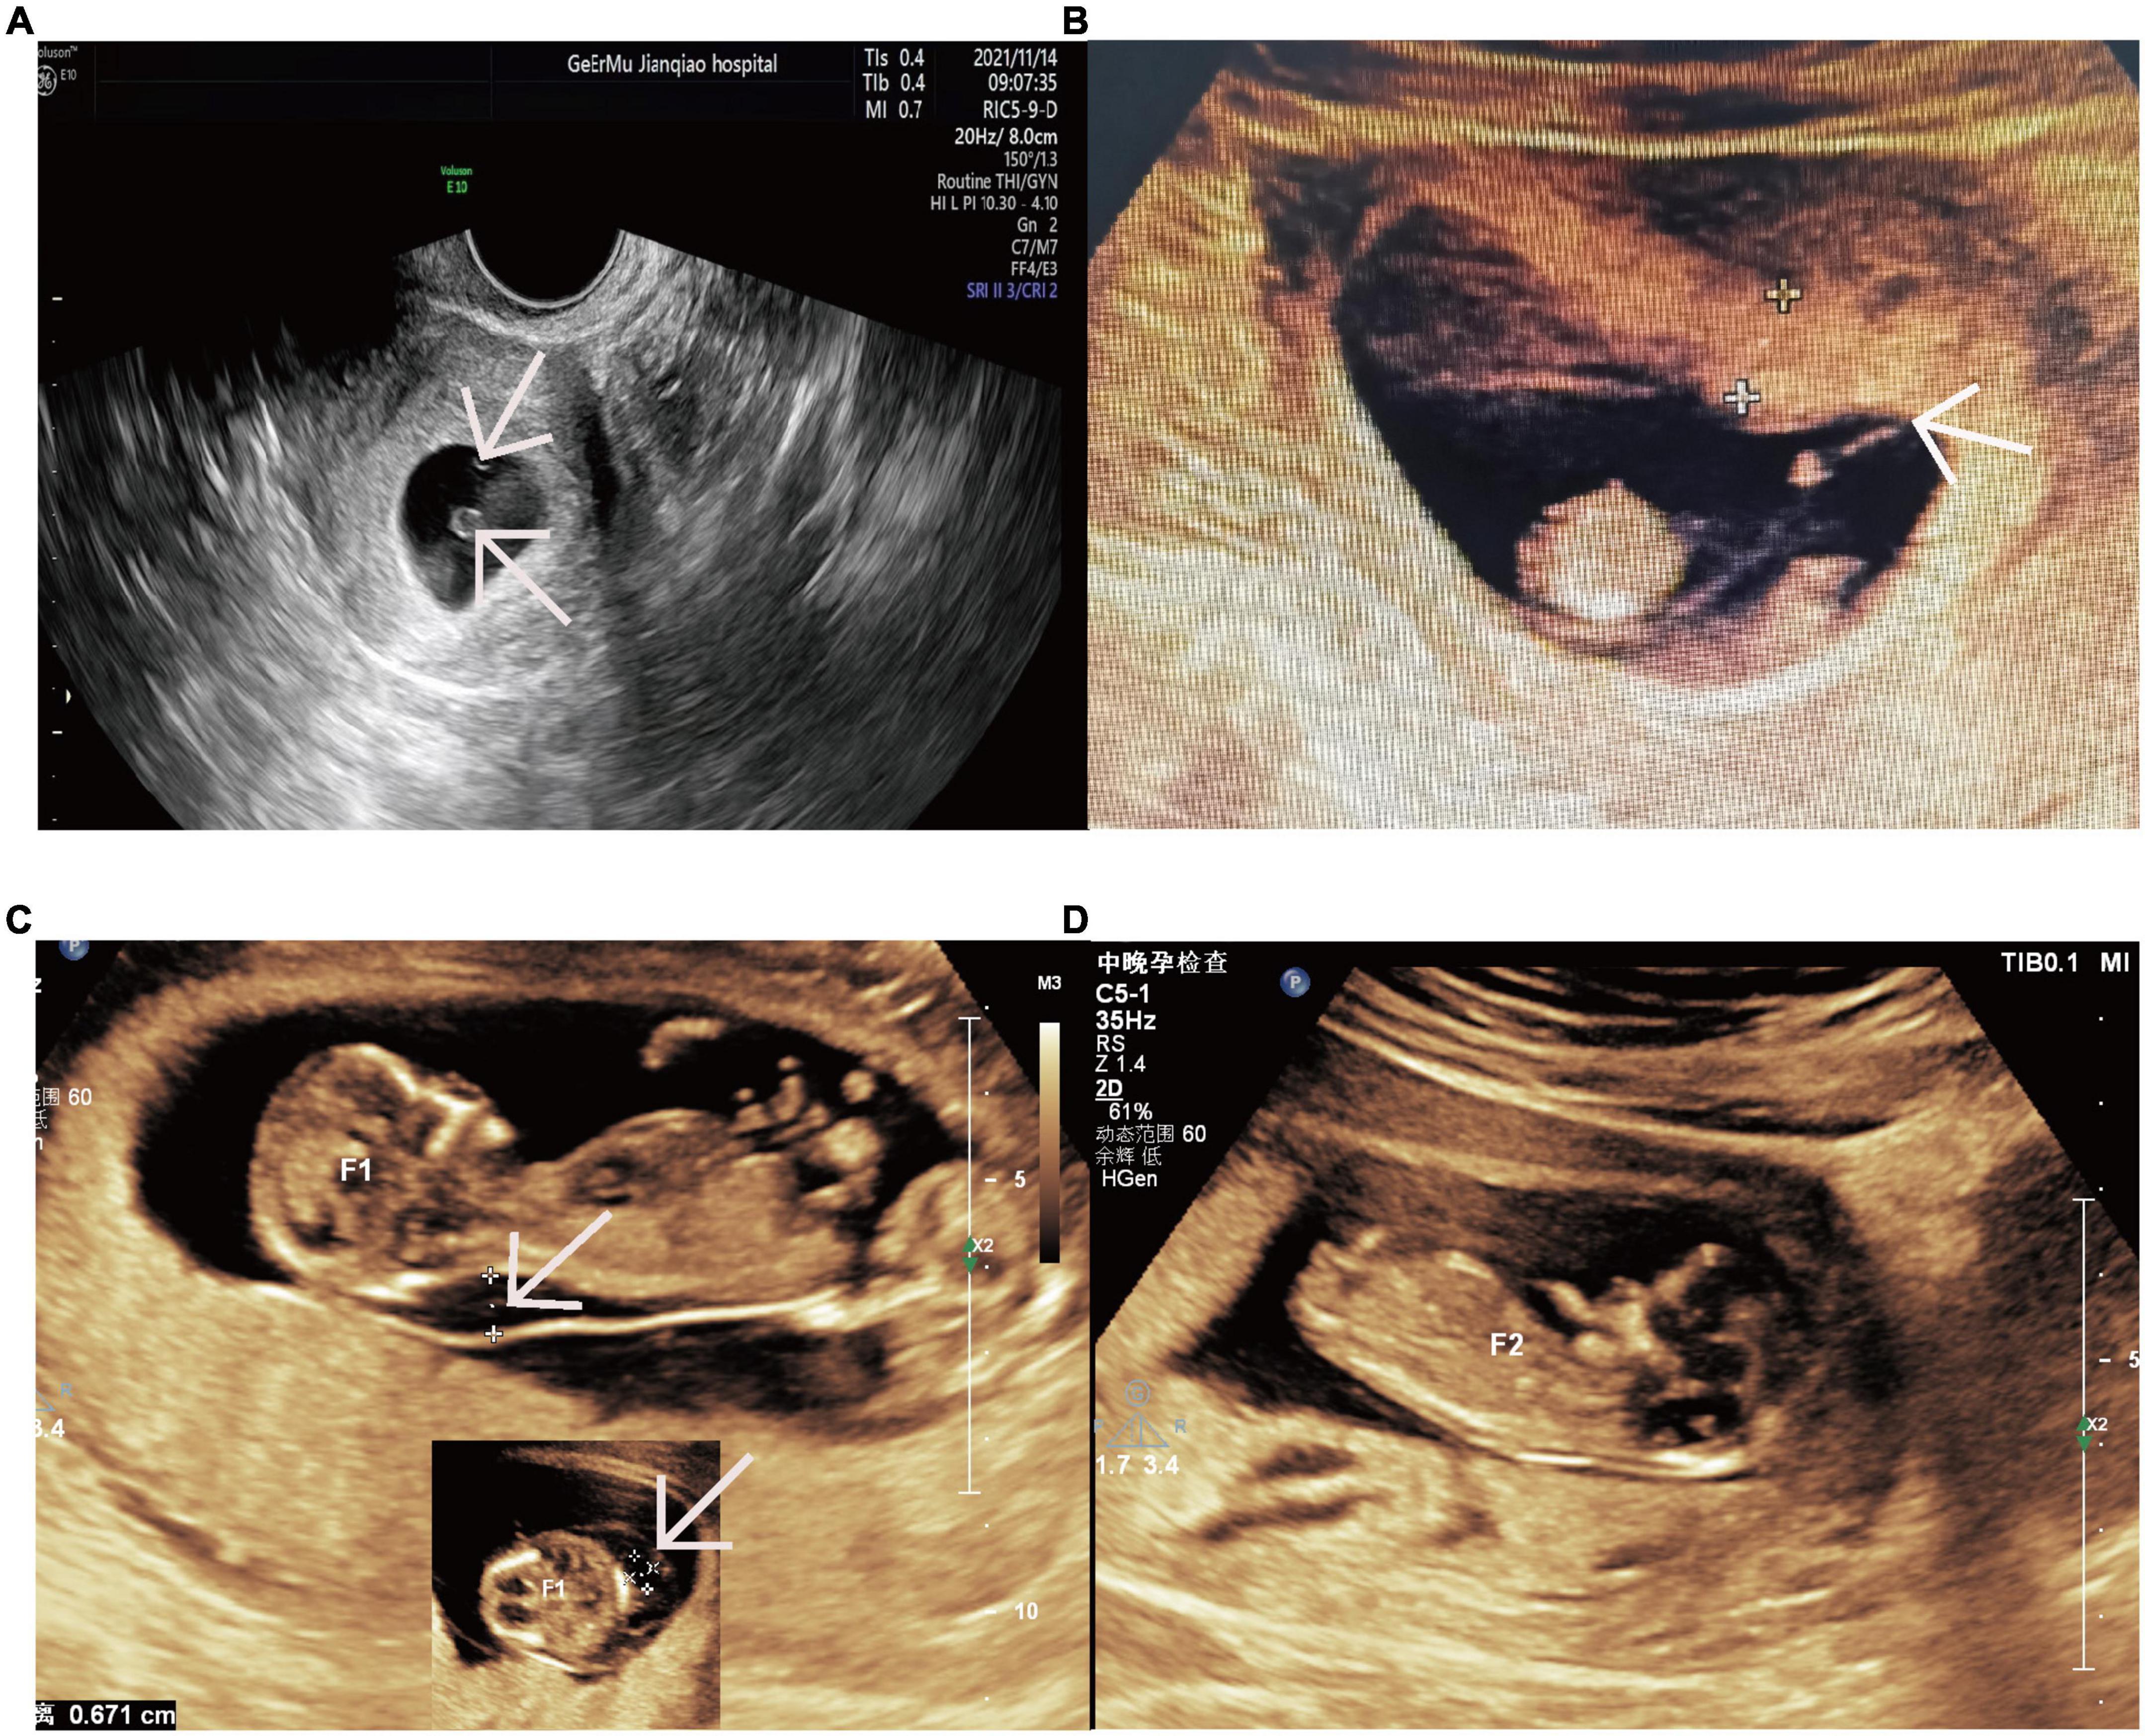

Ensure accurate fetal monitoring with our comprehensive guide to the Toco monitor. Learn how this essential obstetric tool measures uterine contractions and fetal heart rate during labor. Discover how healthcare professionals use electronic fetal monitoring (EFM) to track pregnancy health, interpret tracings, and ensure patient safety throughout the birthing process for optimal maternal and neonatal care outcomes.